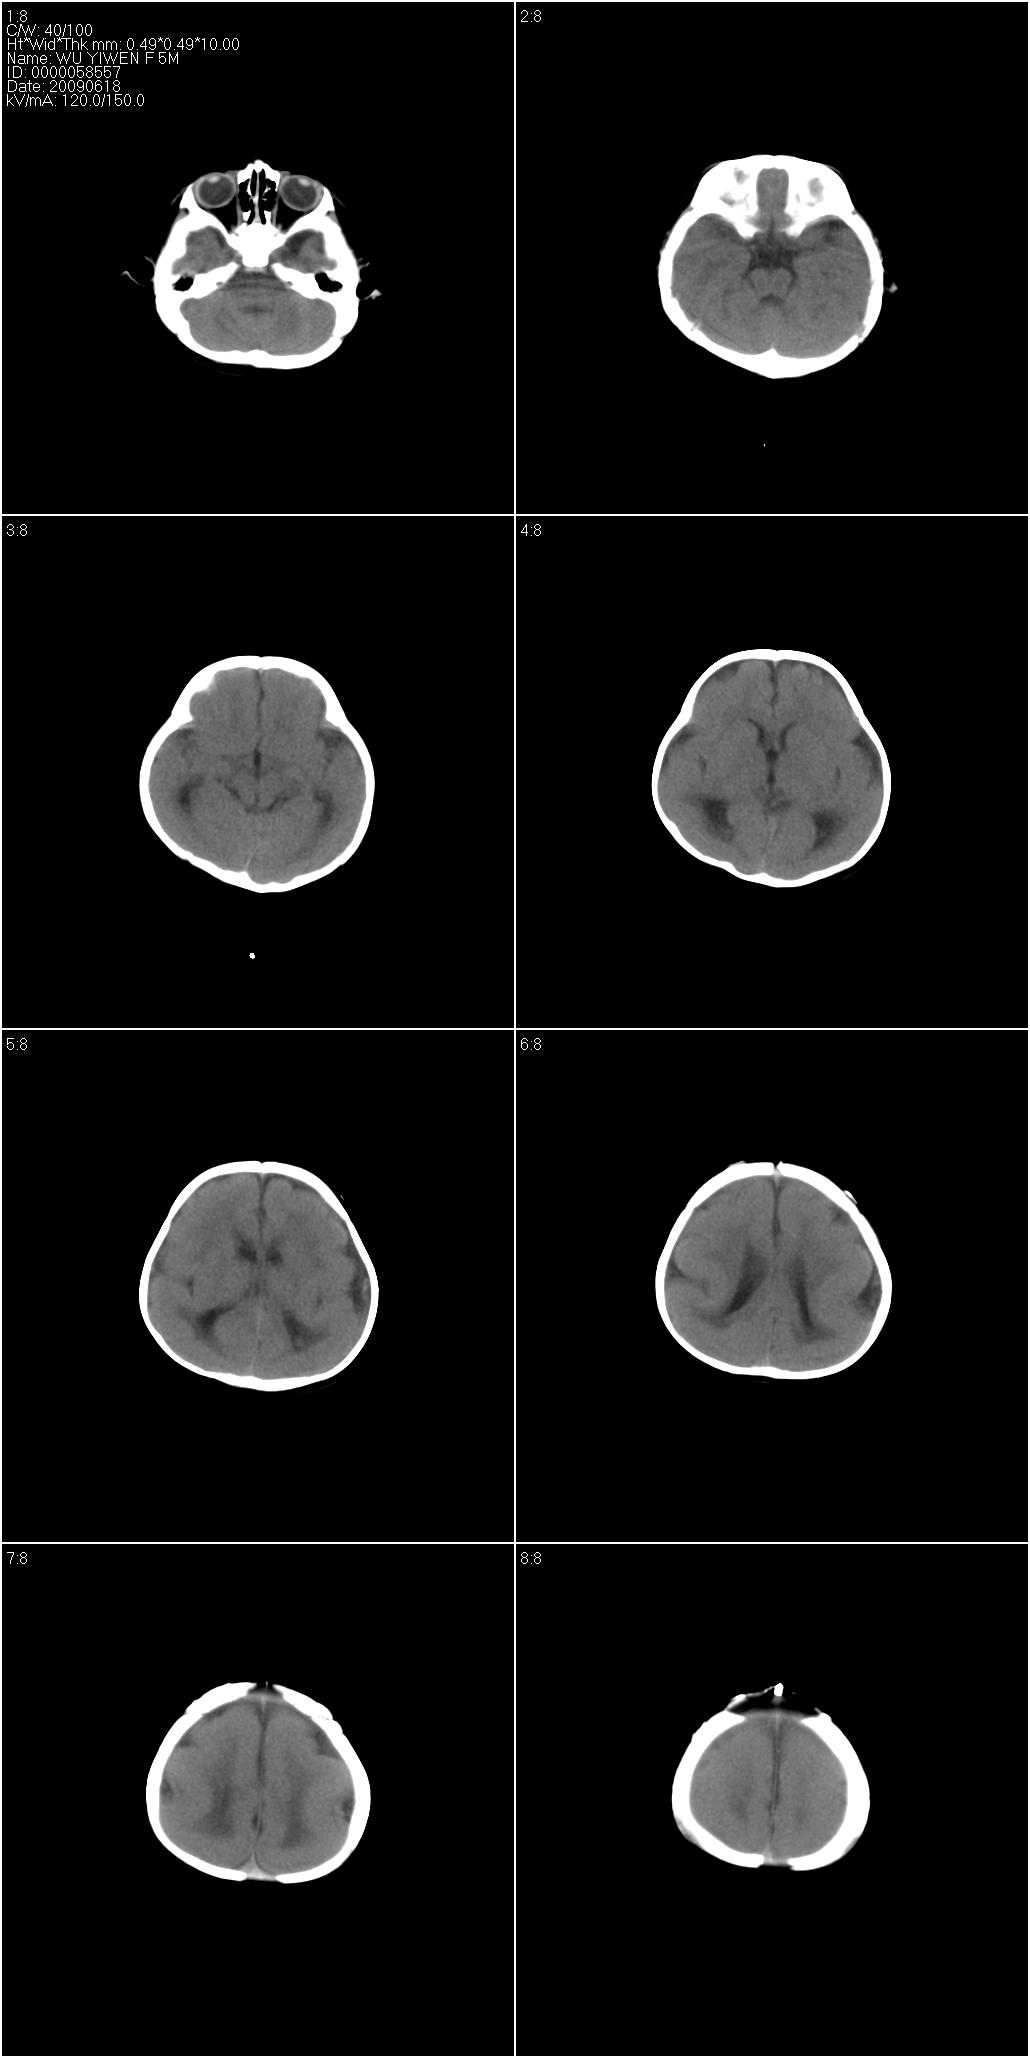

标题: PED1957:男性,5个月。抽风两次。 [打印本页]

标题: PED1957:男性,5个月。抽风两次。

巨脑回

支持巨脑回.脑白质稀少,考虑发育不良.

大脑发育不良(巨脑回为主)

巨脑回看见了,有名有肾上腺脑白质营养不良什么的

支持巨脑回.脑白质稀少,考虑发育不良